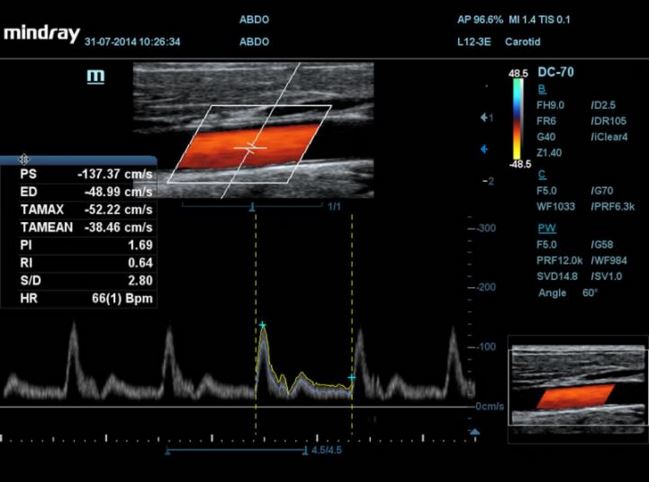

MINDRAY DC-70

Aparat DC-70

Aparat DC-70 daje znacznie więcej. Jego unikalne sterowanie dotykiem i gestem zostało zaprojektowane w taki sposób, by usprawnić płynny obieg czynności. Czystość obrazu uzyskiwana dzięki innowacyjnej technologii głowic w aparacie DC-70 pozwoli wykryć anomalie lub nawet niewielkie zmiany. Narzędzia ułatwiające użytkowanie, obejmujące między innymi wiele pakietów do automatycznych pomiarów pomagają zredukować czas skanowania, standaryzować protokoły badań, zwiększyć produktywność i otoczyć pacjenta jeszcze lepszą opieką.

• HR Flow 2-giej generacji /Przepływy o wysokiej rozdzielczości pozwalające uzyskać niezwykłą rozdzielczość przestrzenną.

Zakres aplikacji z pakietami automatycznych pomiarów obejmuje Smart OB, Smart NT, Smart-V, Auto IMT, Auto LV i automatyczny obrys i zliczanie PW,